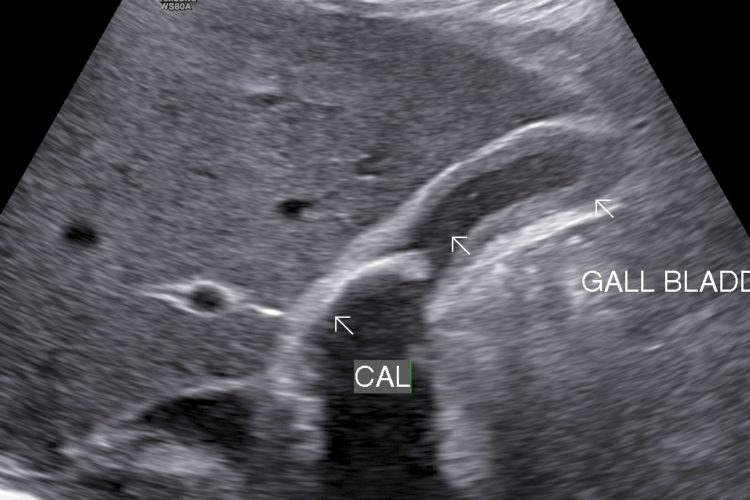

• Cholecystitis: Cholecystitis is Inflammation of gall bladder. Acute calculus cholecystitis results when calculus/calculi get impacted at neck of gall bladder or cystic duct.

• Finding: Sonography shows thickened oedmatous walls of gall bladder & impacted calculi. Sludge, pericholicystic fluid , localized abscess are additional findings. Sometimes gall bladder is so overdistended that impacted calculi may not be visualized.